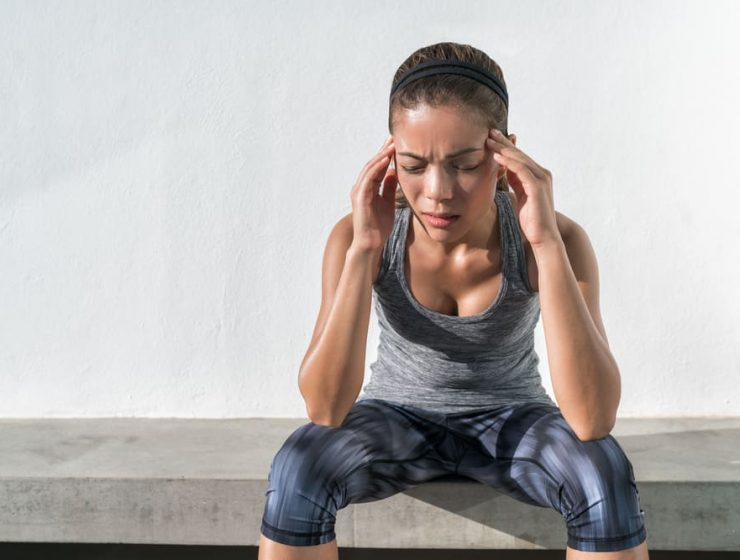

A las personas que sufren de migrañas les aconsejan que practiquen algo de deporte para…